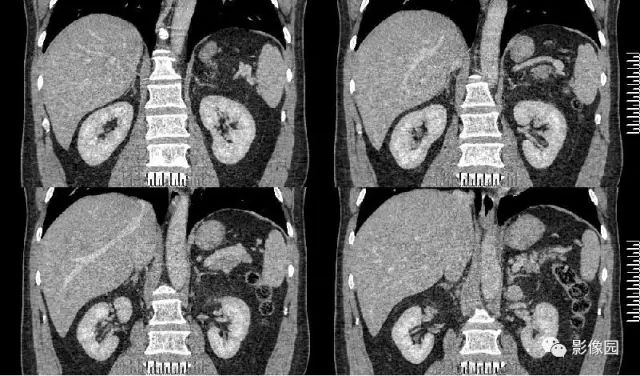

肚肚丫头: 左侧肾上腺见结节状异常密度影,无分叶,边缘光滑,增强扫描呈显著不均匀强化,中心见片状低密度区,考虑:1. 嗜铬细胞瘤;2.腺瘤

【病理结果】左肾上腺嗜铬细胞瘤

影像诊断要点

CT:CT对肿瘤定位可提供较准确信息,诊断准确率高,为常用检查方法。多表现为一侧肾上腺较大圆形或椭圆形肿块,偶为双侧性。直径常为3~5cm,或更大。较小肿瘤密度均一,类似肾脏密度;较大肿瘤常因坏死或陈旧性出血而密度不均,内有单发或多发低密度区,甚至呈囊性表现。少数肿瘤可有高密度钙化灶。增强扫描,肿瘤实体部分明显强化,其内低密度区无强化。